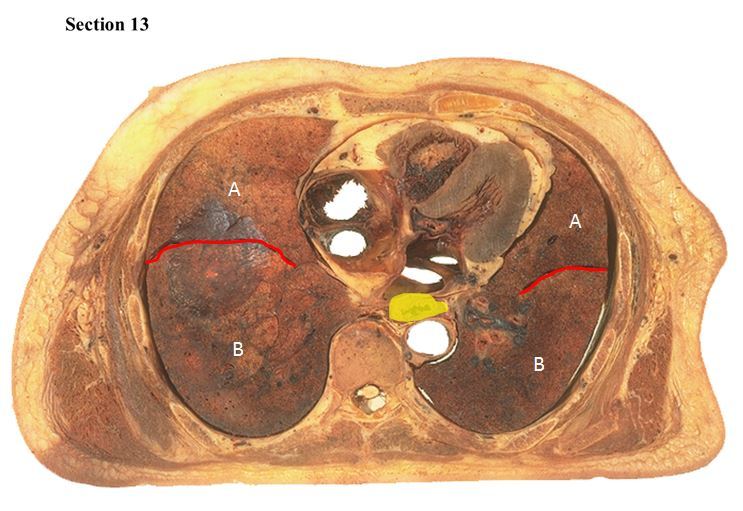

14

Each red line is a/an _____ that separates a structure A which is a/an _____ from a structure B which is a/an _____within each lung.

A

oblique fissure

superior lobe

inferior lobe